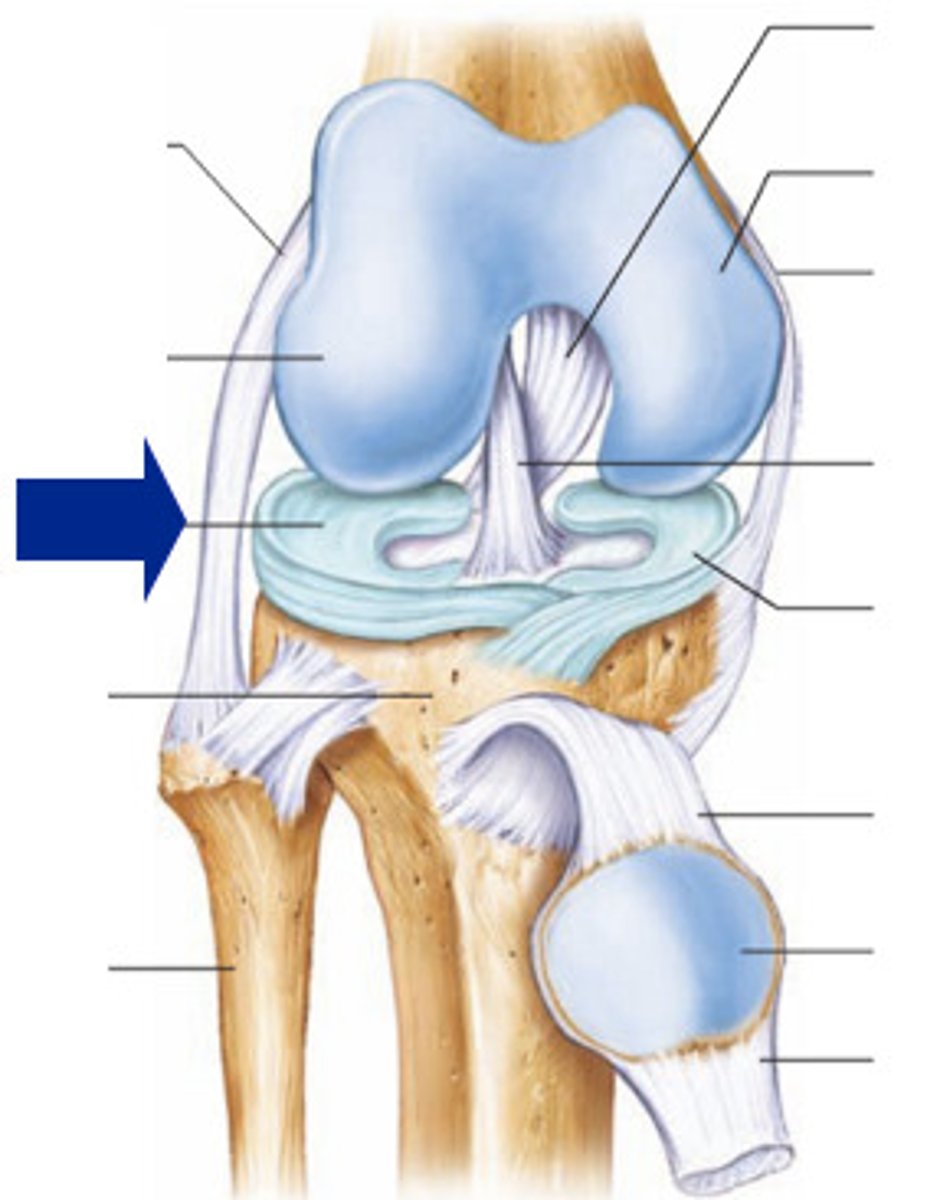

Medial meniscus

Lateral meniscus

Anterior cruciate ligament

Posterior cruciate ligament

Medial (tibial) collateral ligament

Lateral (fibular) collateral ligament